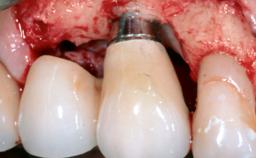

Treatment of Peri-Implant Mucositis at a Zirconia Implant

Recent clinical studies, most with short-to-medium term observation periods, have reported on the favorable clinical performance of zirconia implants in terms of survival rates, clinical, and radiographic outcomes (Roehling and coworkers 2016; Roehling and coworkers 2017; Rodriguez and coworkers 2018; Lorenz and coworkers 2019). Nonetheless, a rather high incidence of peri-implant disease at zirconia implants (39% of implants) was noted throughout a two-year period, highlighting the need for treatment protocols of peri-implant diseases at zirconia implants (Becker and coworkers 2017).